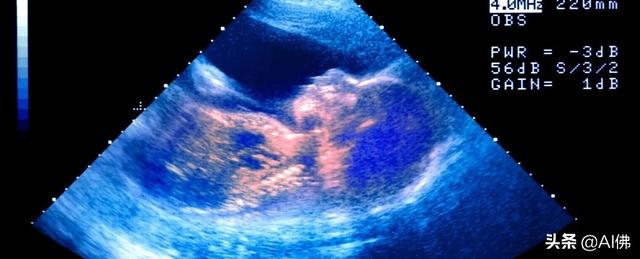

超声波技术使我们能够窥视子宫内部,观察发育中的胎儿。例如,2005年发表在《儿童疾病档案 – 胎儿和新生儿版》杂志上的一段视频显示,一名33周大的胎儿通过超声波侧写做出了看起来像在哭的面部表情。

研究人员用振动和噪音刺激胎儿后,它会张开下巴,把它收起来。随着胸部上升,头部向后倾斜,下颌振动结束,持续进行三次大呼气。在10个胎儿中观察到这种运动(约占扫描婴儿总数的6%)。

上图:2005年研究发现的哭泣信号。

上图:胎儿的超声图像,包括右下角哭闹的脸。